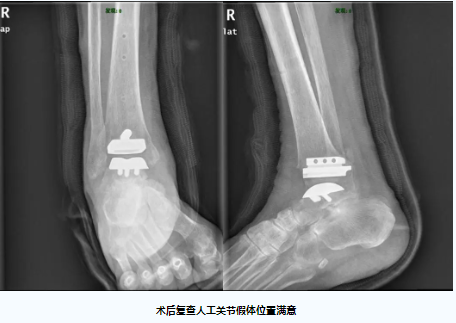

在麻醉手术中心医护团队的精心配合和支持下,经过3个小时的手术,团队成功为高先生植入了全新的踝关节假体,手术出血仅150ml,术后患者疼痛明显缓解,踝关节活动度得到了显著的改善,术后复查的踝关节置换假体位置良好。

人工踝关节置换术是足踝外科领域难度最高的手术之一,标准化的人工关节假体设计精巧,手术操作复杂,手术失败的风险高,对主刀医生的操作有着极高的要求。据文献报道,不少患者因置换手术失败或术后效果不满意而不得不再次行踝关节融合手术进行补救。目前,粤西尚未见独立开展标准化人工踝关节置换术的报道,本次踝关节置换手术取得了良好的治疗效果,得益于关节外科团队巧妙运用了数字骨科3D术前规划技术为高先生进行详尽的计划,有效地避免了许多常见的技术陷阱,本次手术的成功实施,标志着我院足踝外科的人工关节置换技术达到了省内先进水平。